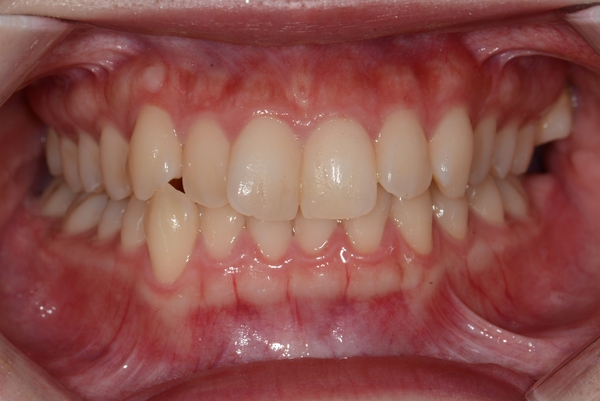

ガタガタとした歯並びや八重歯(叢生)CASE63